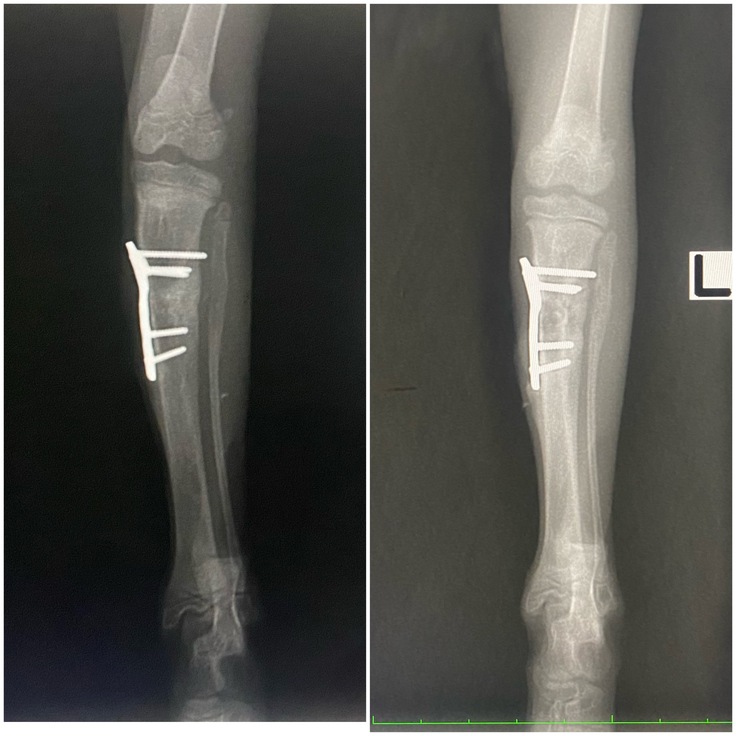

右前足

↑今日 前回8/8↓

前回はまだ亀裂がうっすら残っていましたが、隙間なくしっかりとしっかりと癒合しました🎉

左後足

←今日 前回→

前回とくらべてゴツゴツした感じがなくなりました。古い骨が吸収され新しい骨が形成されていきます。膝より下も骨が伸び、タビちゃんもしっかり成長しています。